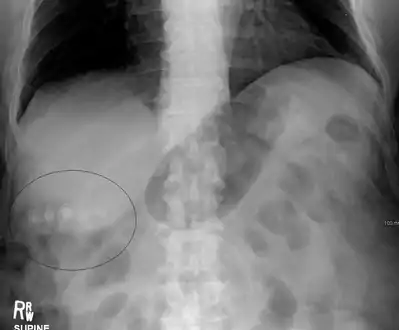

Mixed (brown pigment stones) typically contain 20–80% cholesterol (or 30–70%, according to the Japanese classification system).[36] Other common constituents are calcium carbonate, palmitate phosphate, bilirubin and other bile pigments (calcium bilirubinate, calcium palmitate and calcium stearate). Because of their calcium content, they are often radiographically visible. They typically arise secondary to infection of the biliary tract which results in the release of β-glucuronidase (by injured hepatocytes and bacteria) which hydrolyzes bilirubin glucuronides and increases the amount of unconjugated bilirubin in bile. Between 4% and 20% of stones are mixed.[3]